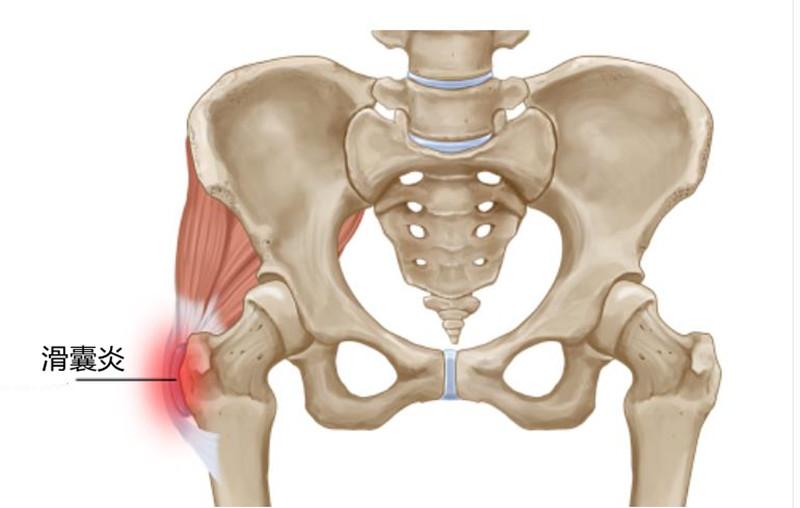

这些症状都指向髋关节滑囊炎,也叫大转子滑囊炎。大转子就是臀部侧面可以摸到突出的骨骼。早期X光很难发现问题。如果不积极治疗,发展下去有可能引起跛行,站立不稳,长短腿,甚至股骨头坏死。

髋关节外侧的滑囊是一种含有液体的囊,它充当骨骼、肌腱和肌肉之间的垫子。人在行走时,骨盆随着身体摆动,当稳定骨盆的髋外展肌过于劳累或者虚弱时,骨盆就不稳了,这时候周围的其他肌肉会来“帮忙”,这也就导致他们被拉伸,继而可能出现滑囊的发炎。